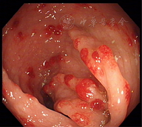

辅助检查:便常规+潜血:潜血阳性;血常规、凝血功能正常;难辨梭菌抗原及毒素检测阴性;血生化白蛋白30.4 g/L、钾3.02 mmol/L,余无明显异常;甲状腺功能T3、T4正常、促甲状腺激素(TSH)0.38 mU/L;结核干扰素测定正常;血清肿瘤标志物正常;血沉2 mm/1 h;CRP正常;类风湿因子(RF)101.9 kU/L;免疫球蛋白IgA、IgM、IgG正常,补体C3 0.672 g/L,补体C4 0.157 g/L;IgG亚类测定四项正常;抗核抗体(ANA)阴性;抗中性粒细胞胞浆抗体(ANCA)阴性;狼疮五项阴性;狼疮抗凝因子试验正常;心磷脂抗体正常;抗着丝点抗体阴性;腹部超声未见异常;甲状腺超声:甲状腺右叶实性结节;胸部CT:双侧胸腔少量积液;胃镜示胃底、胃体、胃窦弥漫性大小不等结节状息肉样隆起(图3),部分融合,表面充血水肿,以胃体、胃窦为重,胃底部可见黏膜下黑褐色素斑沉着(图4),十二指肠降部见散在小息肉样隆起;快速尿素酶法检测幽门螺杆菌阴性;胃窦、胃底、十二指肠降部取病理示慢性炎症;肠镜示回肠末端、盲肠、结肠、直肠广泛充血性息肉样隆起(图5),回肠、近端结肠息肉较小(直径0.1~0.2 cm),远端结肠、直肠息肉较大(直径0.2~0.4 cm)。病理示回肠慢性炎症,伴黏膜糜烂;盲肠增生性息肉,慢性炎症;直肠增生性息肉,慢性炎症,伴腺体囊状扩张。诊断:CCS。